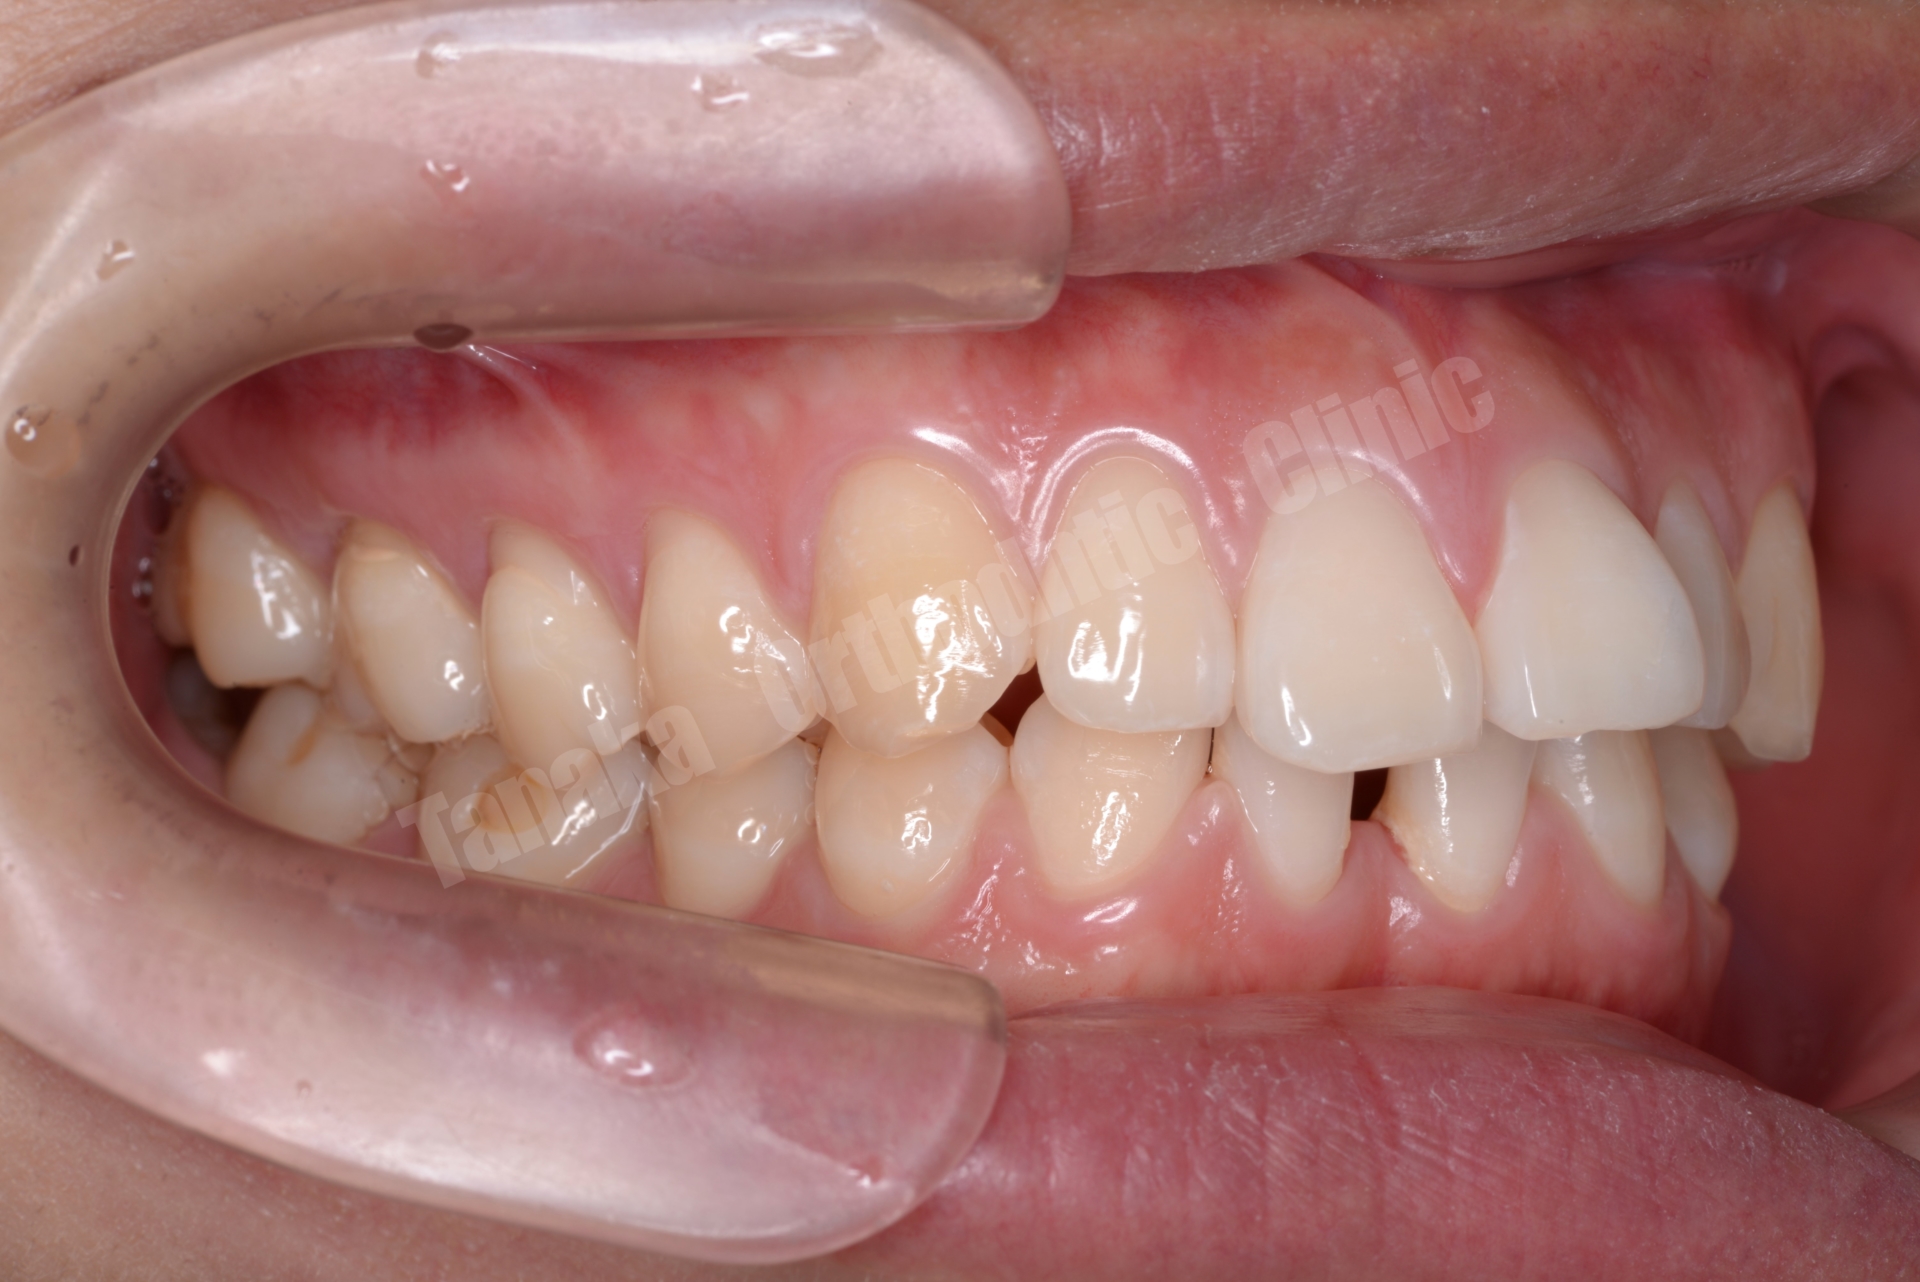

【治療前】

| 診断 | 下顎前歯の先天欠如(2本)によるスペースドアーチ、上顎前歯の唇側傾斜、前歯部水平被蓋が大きい、上顎前歯部叢生、両側AngleⅡ級、上下顎両側8番の埋伏歯、全体的に歯根が短い |